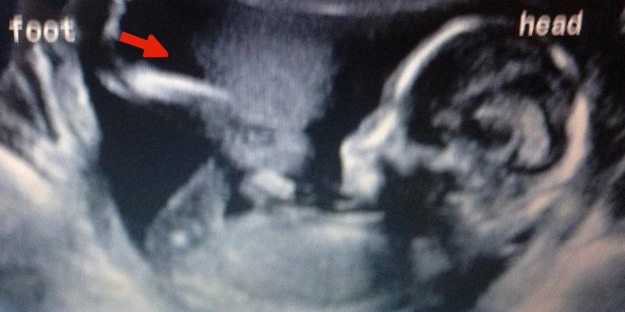

La ecografía es el método más usado por los médicos para mostrar a los futuros padres el crecimiento de su bebé. El primer ultrasonido, sobre todo para las mamás primerizas, es uno de los momentos más emocionantes durante la etapa de embarazo y es que ellas pueden ver por primera vez al niño que pronto tendrán entre sus brazos. Sin embargo, no todas salen felices tras someterse a este procedimiento, pues los resultados a veces revelan curiosidades un poco espeluznantes. Estas son las ecografías más extrañas, pero divertidas a la vez, que las usuarias comparten a través de las redes sociales. La mayoría de las imágenes fueron compartidas por las propias gestantes.